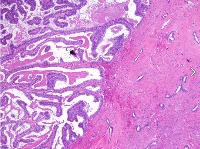

This is an AI laboratory project by Linette Dannah Cartagena, a second year medical student. Ovarian cancer can be classified into four main types: epithelial tumors, germ cell tumors, stromal tumors, and small cell carcinoma of the ovary. This model aims to recognize each type through AI. All one has to do is to simply by upload a photo of the histological slide.